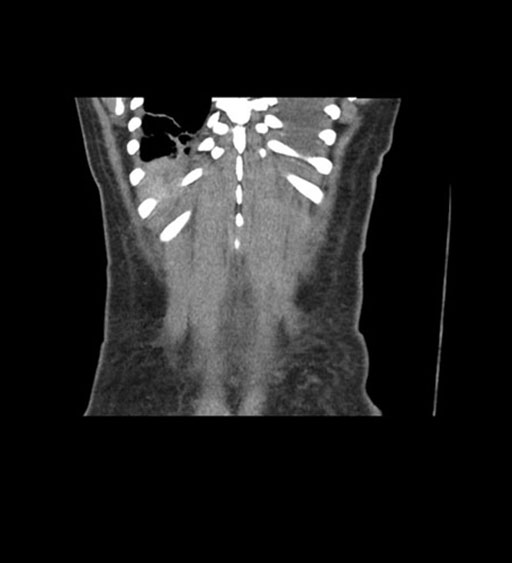

Coronal Arterial

Coronal Venous

Imaging analysis

Based on initial findings, which issue(s) would you be most concerned about?